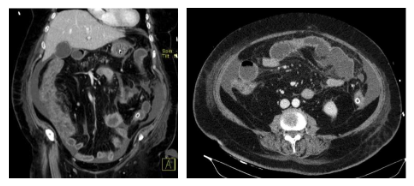

Ao 3º dia de internamento, por presença de hematoquézias foi realizada colonoscopia que evidenciou colite isquémica moderada de todo o cólon. Foi realizada nova TC abdomino-pélvica (Fig. 2) que demonstrou espessamento do cólon, com captação mantida de contraste da parede, sem evidencia de sofrimento de ansas nem pneumoperitoneu, mantendo mínima lâmina de líquido intraperitoneal. Dada a melhoria clínica da doente, com diminuição significativa do suporte aminérgico, diminuição dos parâmetros inflamatórios analíticos e dos lactatos, bom débito urinário, ausência de sinais de irritação peritoneal e os achados já descritos na TC, foi decidido manter abordagem conservadora.

Figura 2: TC abdomino-pélvica realizada no 3º dia de internamento